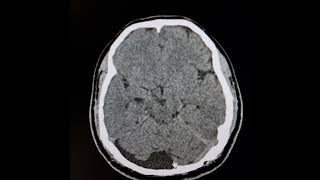

Что такое арахноидальная или арахноидная киста? Янис Шлезиньш, нейрохирург, Доктор медицинских наук

В большинстве случаев арахноидальные кисты являются врожденными и не вызывают никаких симптомов, потому как они не повышают давление внутри черепа (кисты либо очень маленького размера, либо они не вызывают симптомов, потому что у них самих внутри нет повышенного давления). Следовательно, пациент может узнать о существовании кисты только в таком случае, если головной мозг исследуется по какой-либо другой причине. Поскольку в стенке арахноидальной кисты могут быть небольшие кровеносные сосуды, в случае головной травмы эти кровеносные сосуды могут лопнуть и вызвать кровоизлияние как в мозг, так и во внутреннюю часть кисты. Таким образом, пациенты с бессимптомными арахноидальными кистами подвергаются повышенному риску значительных внутричерепных кровоизлияний в случае травмы головы. В случае если кровоизлияние значительного размера пациенту может потребоваться срочная / неотложная операция по жизненным показаниям – удаление внутричерепного кровоизлияния. В более редких случаях, когда арахноидальная киста имеет большие размеры и / или оказывает давление на окружающие структуры мозга, киста может вызывать головную боль, тошноту, головокружение, эпилептические припадки, нарушения циркуляции спинномозговой жидкости (гидроцефалию) а также и специфические симптомы в зависимости от конкретных частей мозга на которые киста оказывает давление (задержка развития, поведенческие изменения, неспособность контролировать произвольные движения – атаксия, нарушение баланса). Есть также случаи, когда киста вызывает слабость или паралич на одной стороне тела (гемипарез). В детском возрасте вызванное кистой высокое давление внутри черепа (повышенное внутричерепное давление) также может привести к различным черепным аномалиям, а также к увеличению размера головы (макроцефалия). В дополнение к гидроцефалии, кисты в так называемой супраселлярной области могут быть связаны с нарушениями зрения и гормональными изменениями, поскольку давление, которое они оказывают, может влиять на центры гормональной регуляции в головном мозге, которые могут также включать нарушения менструального цикла, нарушения скорости роста, отклонения в физическом развитии и др.